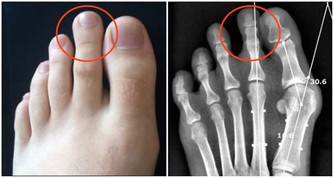

3、皮膚和趾甲的改變

由於雙腿的血液供應以及營養物質不充足,病人的雙腳或雙腿可能出現毛髮減少、生長緩慢,

腿上的皮膚會發亮,腳趾甲變厚而且長得很慢。